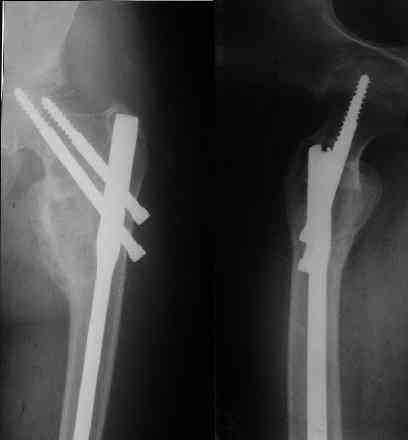

Под рукой нашелся повод для похожих эмоций. Патологический перелом на месте рецидива костной кисты у девочки 16 лет (обсуждали этот случай

года два назад). Ни коллапана, ни трансплантатов, ничего другого в очаг не вводили, кроме нержавеющей стали. Она, видимо, тоже остеоиндуктор - видно, что на месте пустоты через несколько месяцев кость.